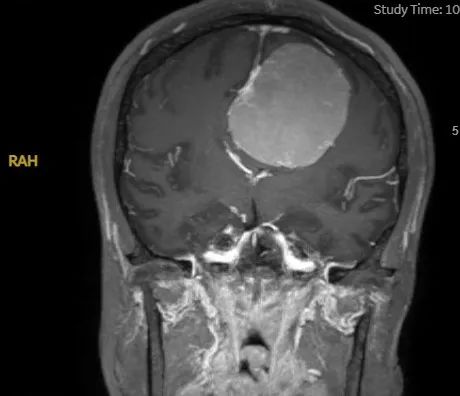

11月15日,潘女士来到昆山市一医院神经外科就诊,查CT见巨大颅内占位,立即安排住院,通过放射科绿色通道安排,第2天进行了核磁共振(MRI)平扫+增强检查,结果显示:纵裂硬脑膜脑膜瘤(大小约60*56.5*58mm)。

手术前